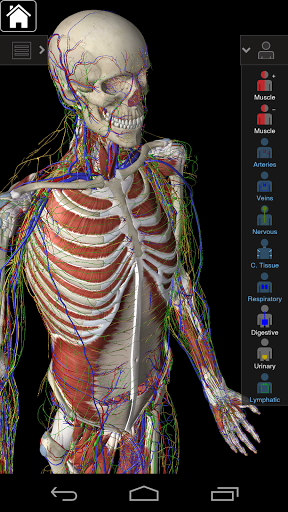

Це додаток включає в себе важливу анатомію для 10 систем:

⁃Скелетні

⁃Маски

⁃Сполучна тканина

⁃Винис

⁃ Артерії

⁃Nerves

⁃ респіраторний

⁃ дизельний

⁃ Урядовий

⁃Lymphatic

⁃все також включає в себе мозок і серце

Безперервна навігація та функціональність

Розумна функціональність, знайдена в додатку, дозволяє користувачеві знімати шари м'язів за допомогою інструмента «скальпель». Ця програма надає користувачам можливість увімкнення / вимкнення систем без необхідності скасувати вибір окремих структур або переплутати через безліч попередньо визначених регіональних вкладок, як і інші програми.